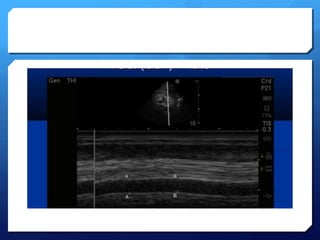

Assessing the IVC

 During inspiration, intrathoracic pressure becomes more

negative, abdominal pressure becomes more positive,

resultant increase in the pressure gradient between the

supra and infra-diaphragmatic vena cava, increases

venous return to the heart.

 Given the extrathoracic IVC is a very compliant vessel

this causes diameter of IVC to decrease with normal

inspiration.

 In patients with low intravascular volume, the inspiration

to expiration diameters change much more than those

who have normal or high intravascular volume.

Estimating theCVP

IVC Diameter (mm) % collapse Estimated CVP (cm

H2O)

<20 >50 5

<20 <50 10

>20 <50 15

>20 0 20

Right atrial pressures, representing central venous pressure, can be estimated

by viewing the respiratory change in the diameter of the IVC.

American society of Echocardiography

2010 guidelines